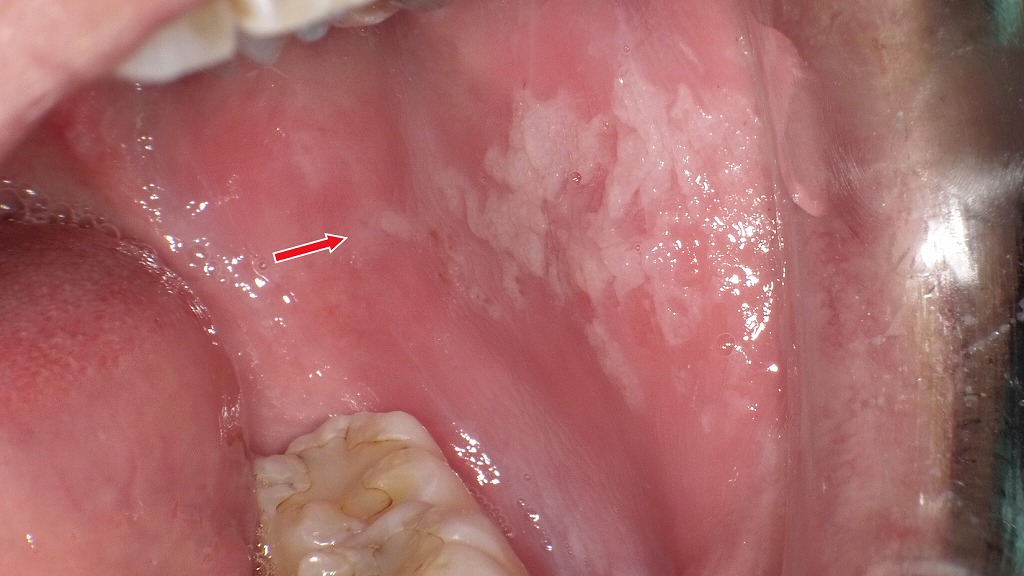

歯ぐきにできたアフタ性口内炎

画像には、**歯肉(歯ぐき)に発生したアフタ性口内炎(アフタ性潰瘍)**の典型的な所見がみられます。

🔍 観察ポイント

- 場所:下の前歯の歯肉(唇側)

- 形状:楕円形〜円形の浅い潰瘍

- 色調:中央が白〜黄白色、周囲が赤く炎症を伴う

- 大きさ:数ミリ程度

- 周囲組織:歯肉は全体的にピンクで、病変部のみ白濁

アフタ性口内炎として非常に典型的な見た目です。

🦷 考えられる状態

アフタ性口内炎(歯肉アフタ)

舌や頬粘膜に比べると歯肉にアフタができる頻度はやや少なめですが、

ストレス・免疫低下・ビタミン不足・疲労・歯ブラシの摩擦などを契機に歯肉にも発生します。

🧪 鑑別が必要な場合

以下の場合は、アフタ以外の疾患(白板症、扁平苔癬、ヘルペスなど)の可能性も考慮します:

- 2週間以上治らない

- 周囲に硬さがある

- 次々に同じ場所に再発する

- 病変が広がる

頬粘膜にみられる白板症の典型所見

頬粘膜に白色の角化した病変が広がっている状態です。擦っても取れない白斑が特徴で、慢性的な刺激(噛み癖・義歯・喫煙など)が原因になることがあります。白板症は前がん病変の一つとされ、確実な診断と経過観察が重要です。